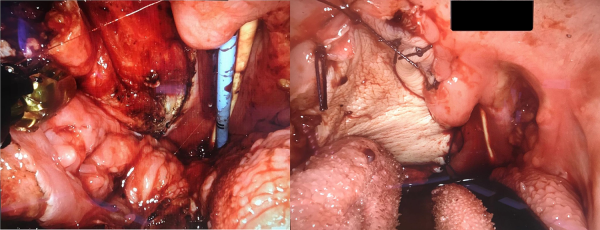

Access to the oropharynx is achieved with a Boyle-Davis gag and a silk stitch placed through the tip of the tongue to provide anterior retraction. The daVinci robot arms and camera are then introduced transorally with an assistant providing suction and retraction as required. The tumor is identified and excised with wide macroscopic margins. Hemostasis is achieved with floseal hemostatic matrix and bipolar diathermy. During this stage, the RFFF is harvested by the plastic surgical team. The graft is then introduced into the oral cavity and the vascular pedicle is tunneled under the digastric muscle to the external neck where a microvascular end-to-end anastomosis is performed to the previously identified donor vessels. The flap is inset within the oropharynx under robotic control with 3/0 sutures. The neck is then closed in layers with a penrose drain left in situ. Intraoperative clinical photographs are shown in Figure 2.

Figure 2

Intraoperative clinical photographs. LEFT, a right-sided oropharyngeal defect can be seen following transoral robotic excision of recurrent oropharyngeal cancer. The tongue base is seen inferiorly and the uvula superiorly. Nasogastric and endonasal tracheal tubes are seen centrally. RIGHT, the same right sided defect after primary closure with robotic-assisted radial forearm free flap.